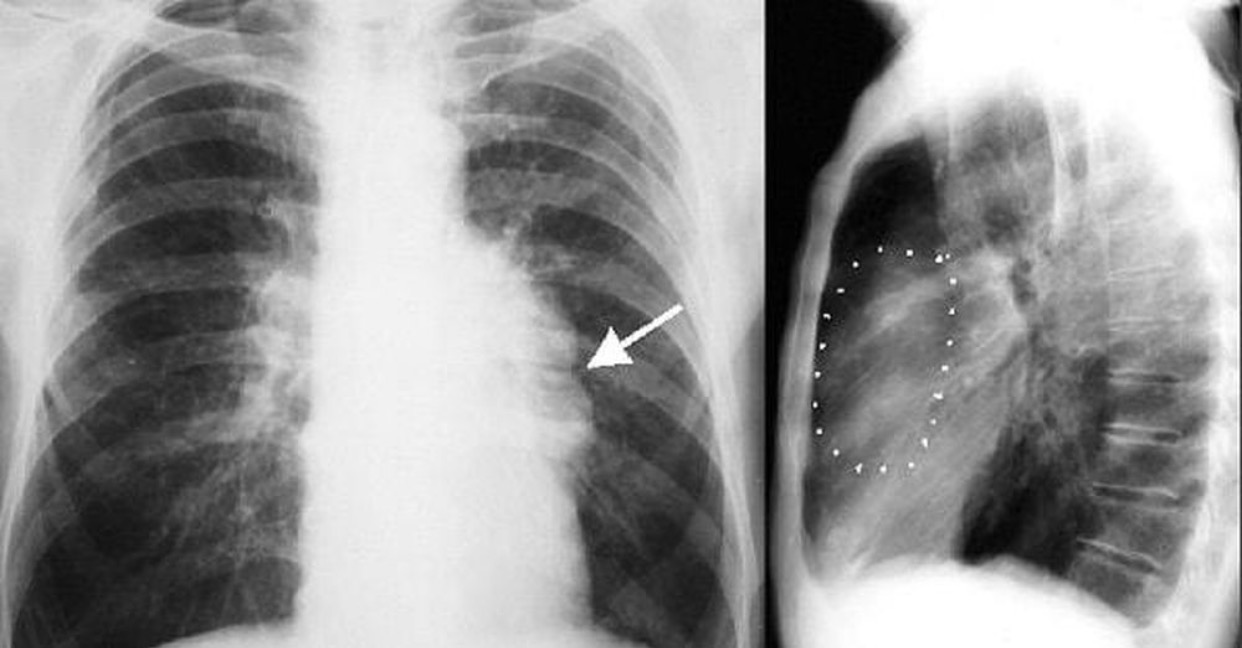

Hình ảnh u trung thất trên phim X quang của bệnh nhân

U trung thất thường không có triệu chứng, có thể tiến triển một cách âm thầm, lớn dần, chèn ép hoặc xâm lấn các cấu trúc quan trọng lân cận như tim, phổi, mạch máu lớn, nếu điều trị trễ có thể nguy hiểm tính mạng bệnh nhân. Người dân nên đi khám sức khỏe định kỳ khi cần thiết sẽ được bác sĩ chỉ định chụp X-quang tim phổi thẳng hoặc CT scan ngực để phát hiện u trung thất sớm.